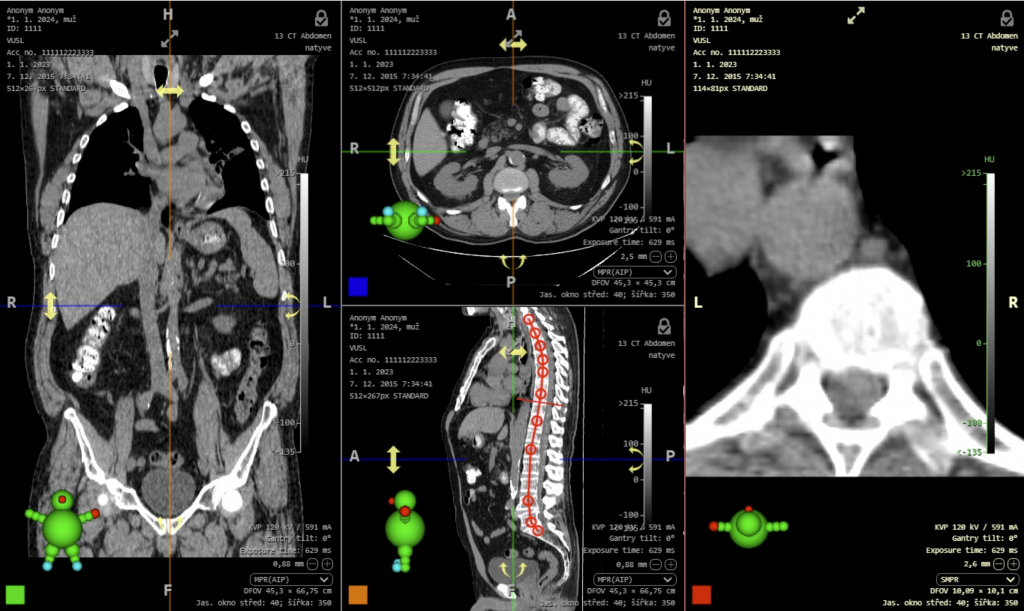

- Úhly dolní končetiny jsou v této verzi DICOM prohlížeče upraveny a nyní zobrazují také laterality úhlů. Lateralitu úhlů je možné určit pomocí pravého postranního panelu v „Pracovní sadě nástrojů měření“, rozbalovacího menu „Lateralita“ v záložce „Úhly dolní končetiny“. Po naměření úhlů dolní končetiny jsou zobrazeny tyto úhly:

- HKA – hip-knee-ankle angle

- mLDFA – mechanical lateral distal femoral angle

- mPTA – medial proximal tibial angle

- JLCA – joint line convergence angle